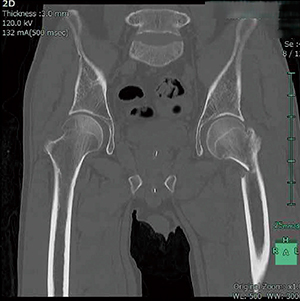

■症例2:大腿骨骨頭部骨折症例

MPR画像により、転子部骨折の部位や範囲を正確に把握することができる。